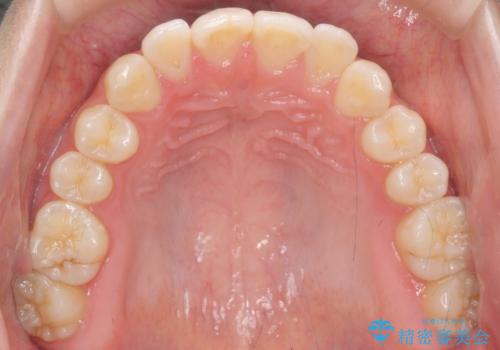

咬んでも向こう側が見える、前歯が閉じない症状でした。また、上の前歯が少し前に出ている状態でした。

上の前歯をわずかに削る処置を行い、後ろに下げながら下の歯となるべく咬むように矯正治療を行いました。

治療前に、患者様が矯正ではなくセラミッククラウンで前歯をかぶせる治療についても気にされてました。

歯の位置が悪く、下の歯と咬まない為咬ませようとすると長い歯になる上に、神経をとらないとひっこめることが難しいと説明を行い、矯正治療をおすすめし、行うこととなりました。